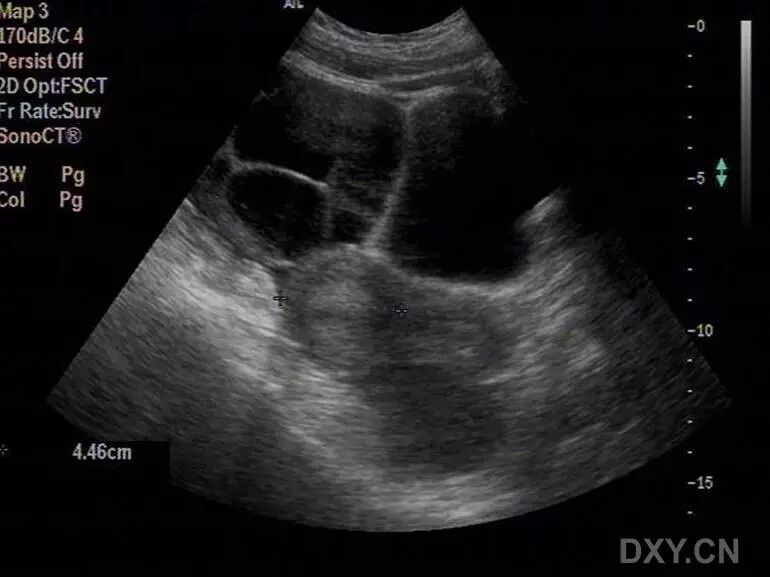

病例1(由丁香园注册用户「微蓝水色」提供):26岁女性,已婚,自觉腹胀不适就诊。

超声检查发现子宫大小正常,双侧附件区多囊性包块,盆腔大量积液,胸腔积液。肝胆胰腺肾脏及膀胱未见明显异常声像。

追问病史,患者多囊卵巢治疗后拟怀孕,最近正服用促排卵药物。

患者治疗后两周复查,盆腹腔积液消失,胸腔少量积液,附件包块明显缩小,能够分辨出卵巢形态。

结合病史,考虑为卵巢过度刺激综合征表现。

以下图片为第一次检查时的图片:

图1 显示子宫周边积液

图2 和图3 显示卵巢增大,其内见多个增大的卵泡样结构